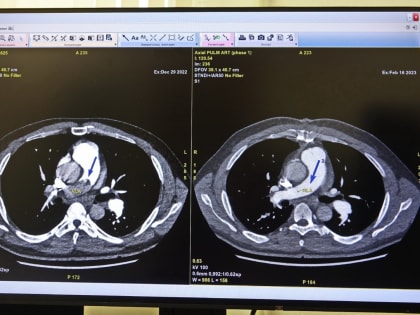

Кардиохирурги Сургута спасли пациента с огромным тромбом, которые препятствовал дыханию

Командная, профессиональная работа врачей в очередной раз доказала — в Югре медицина высоких технологий представлена на высоком уровне.